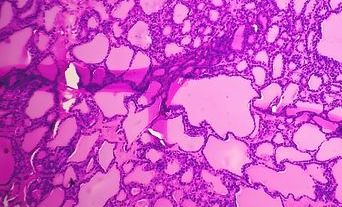

Autopsy webinar series - Diabetes an the heart